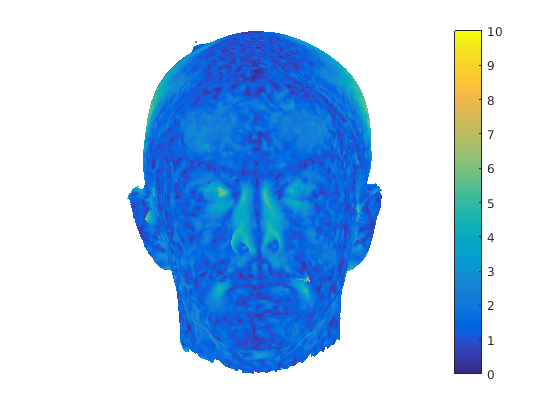

Following this, OSNR ICP iterates over a set of decreasing mesh stiffnesses (typically 10), until the registration between the template and the scan is below some error or a maximum number of iterations is reached. Figure 28 shows a selection of template warp results. The template appears to be accurately warped onto the scan, at least in the normal direction of the surfaces, it is not possible to see error tangential to the surface. Furthermore, we have noted errors on some scans on the ears. To improve these we need a method of automatically landmarking the ears, which is an area for further work.

|

|

|

|

|

|

|

|

The first two modes of head variation are shown in figures 29 and 30. These include the cranial height / facial angle mode and the (almost) pure size mode, as seen in the sagittal profile model.